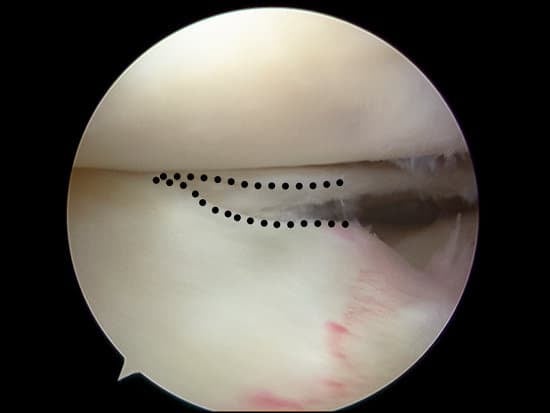

관절경: 관절 내시경을 이용하여 무릎 관절 내부를 직접 확인하고, 손상 부위를 평가합니다. 필요 시 치료도 동시에 시행할 수 있습니다.

관절경 수술: 관절경을 이용하여 파열된 연골을 제거하거나 봉합합니다.

봉합술: 파열된 연골을 봉합하여 자연 치유를 돕습니다. 젊고 활동적인 환자에게 주로 시행됩니다.